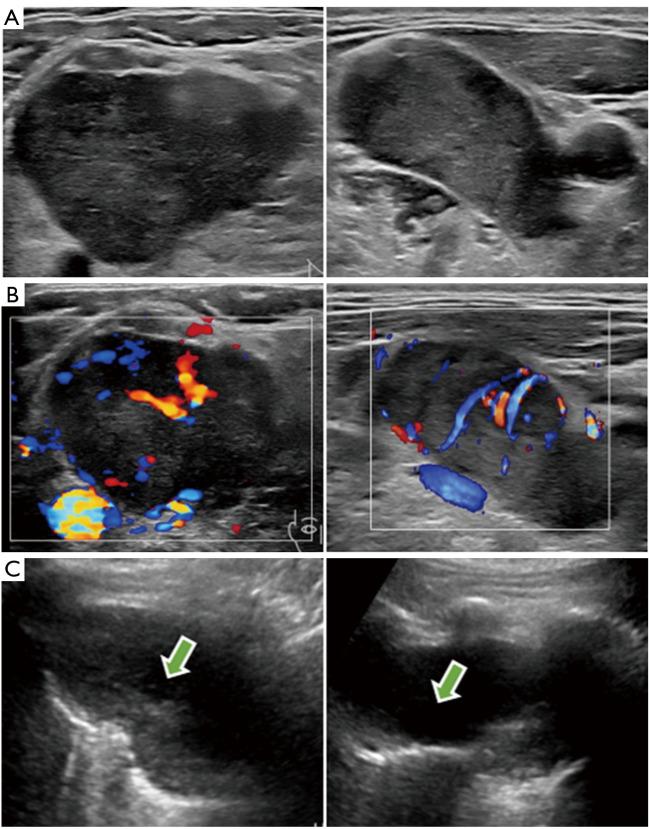

Herein, we report a 51-year-old man who came to our hospital with multiple enlarged lymph nodes in the chest after a computed tomography (CT) examination at another hospital. The patient underwent conventional ultrasound (US), contrast-enhanced ultrasound (CEUS), magnetic resonance imaging (MRI), F-fluorodeoxyglucose positron emission tomography/CT (PET/CT), and finally confirmed the diagnosis of SMARCA4-UT by US-guided puncture biopsy. After symptomatic management, the patient was transferred to another hospital and we performed a short-term follow-up.

CONCLUSIONS

During this procedure, we obtained a series of relevant clinical and imaging data, especially US and CEUS images, which were described for the first time, offering valuable imaging information that will contribute to the clinical diagnosis of this disease to a certain extent. Moreover, this case highlights the efficacy of CEUS in identifying internal necrosis within tumors and lymph nodes, thereby improving the success rate of obtaining tumor tissue for pathological diagnosis. These findings substantiate the practical utility of US and CEUS in the context of mediastinal SMARCA4-UT, emphasizing their potential for widespread clinical adoption.